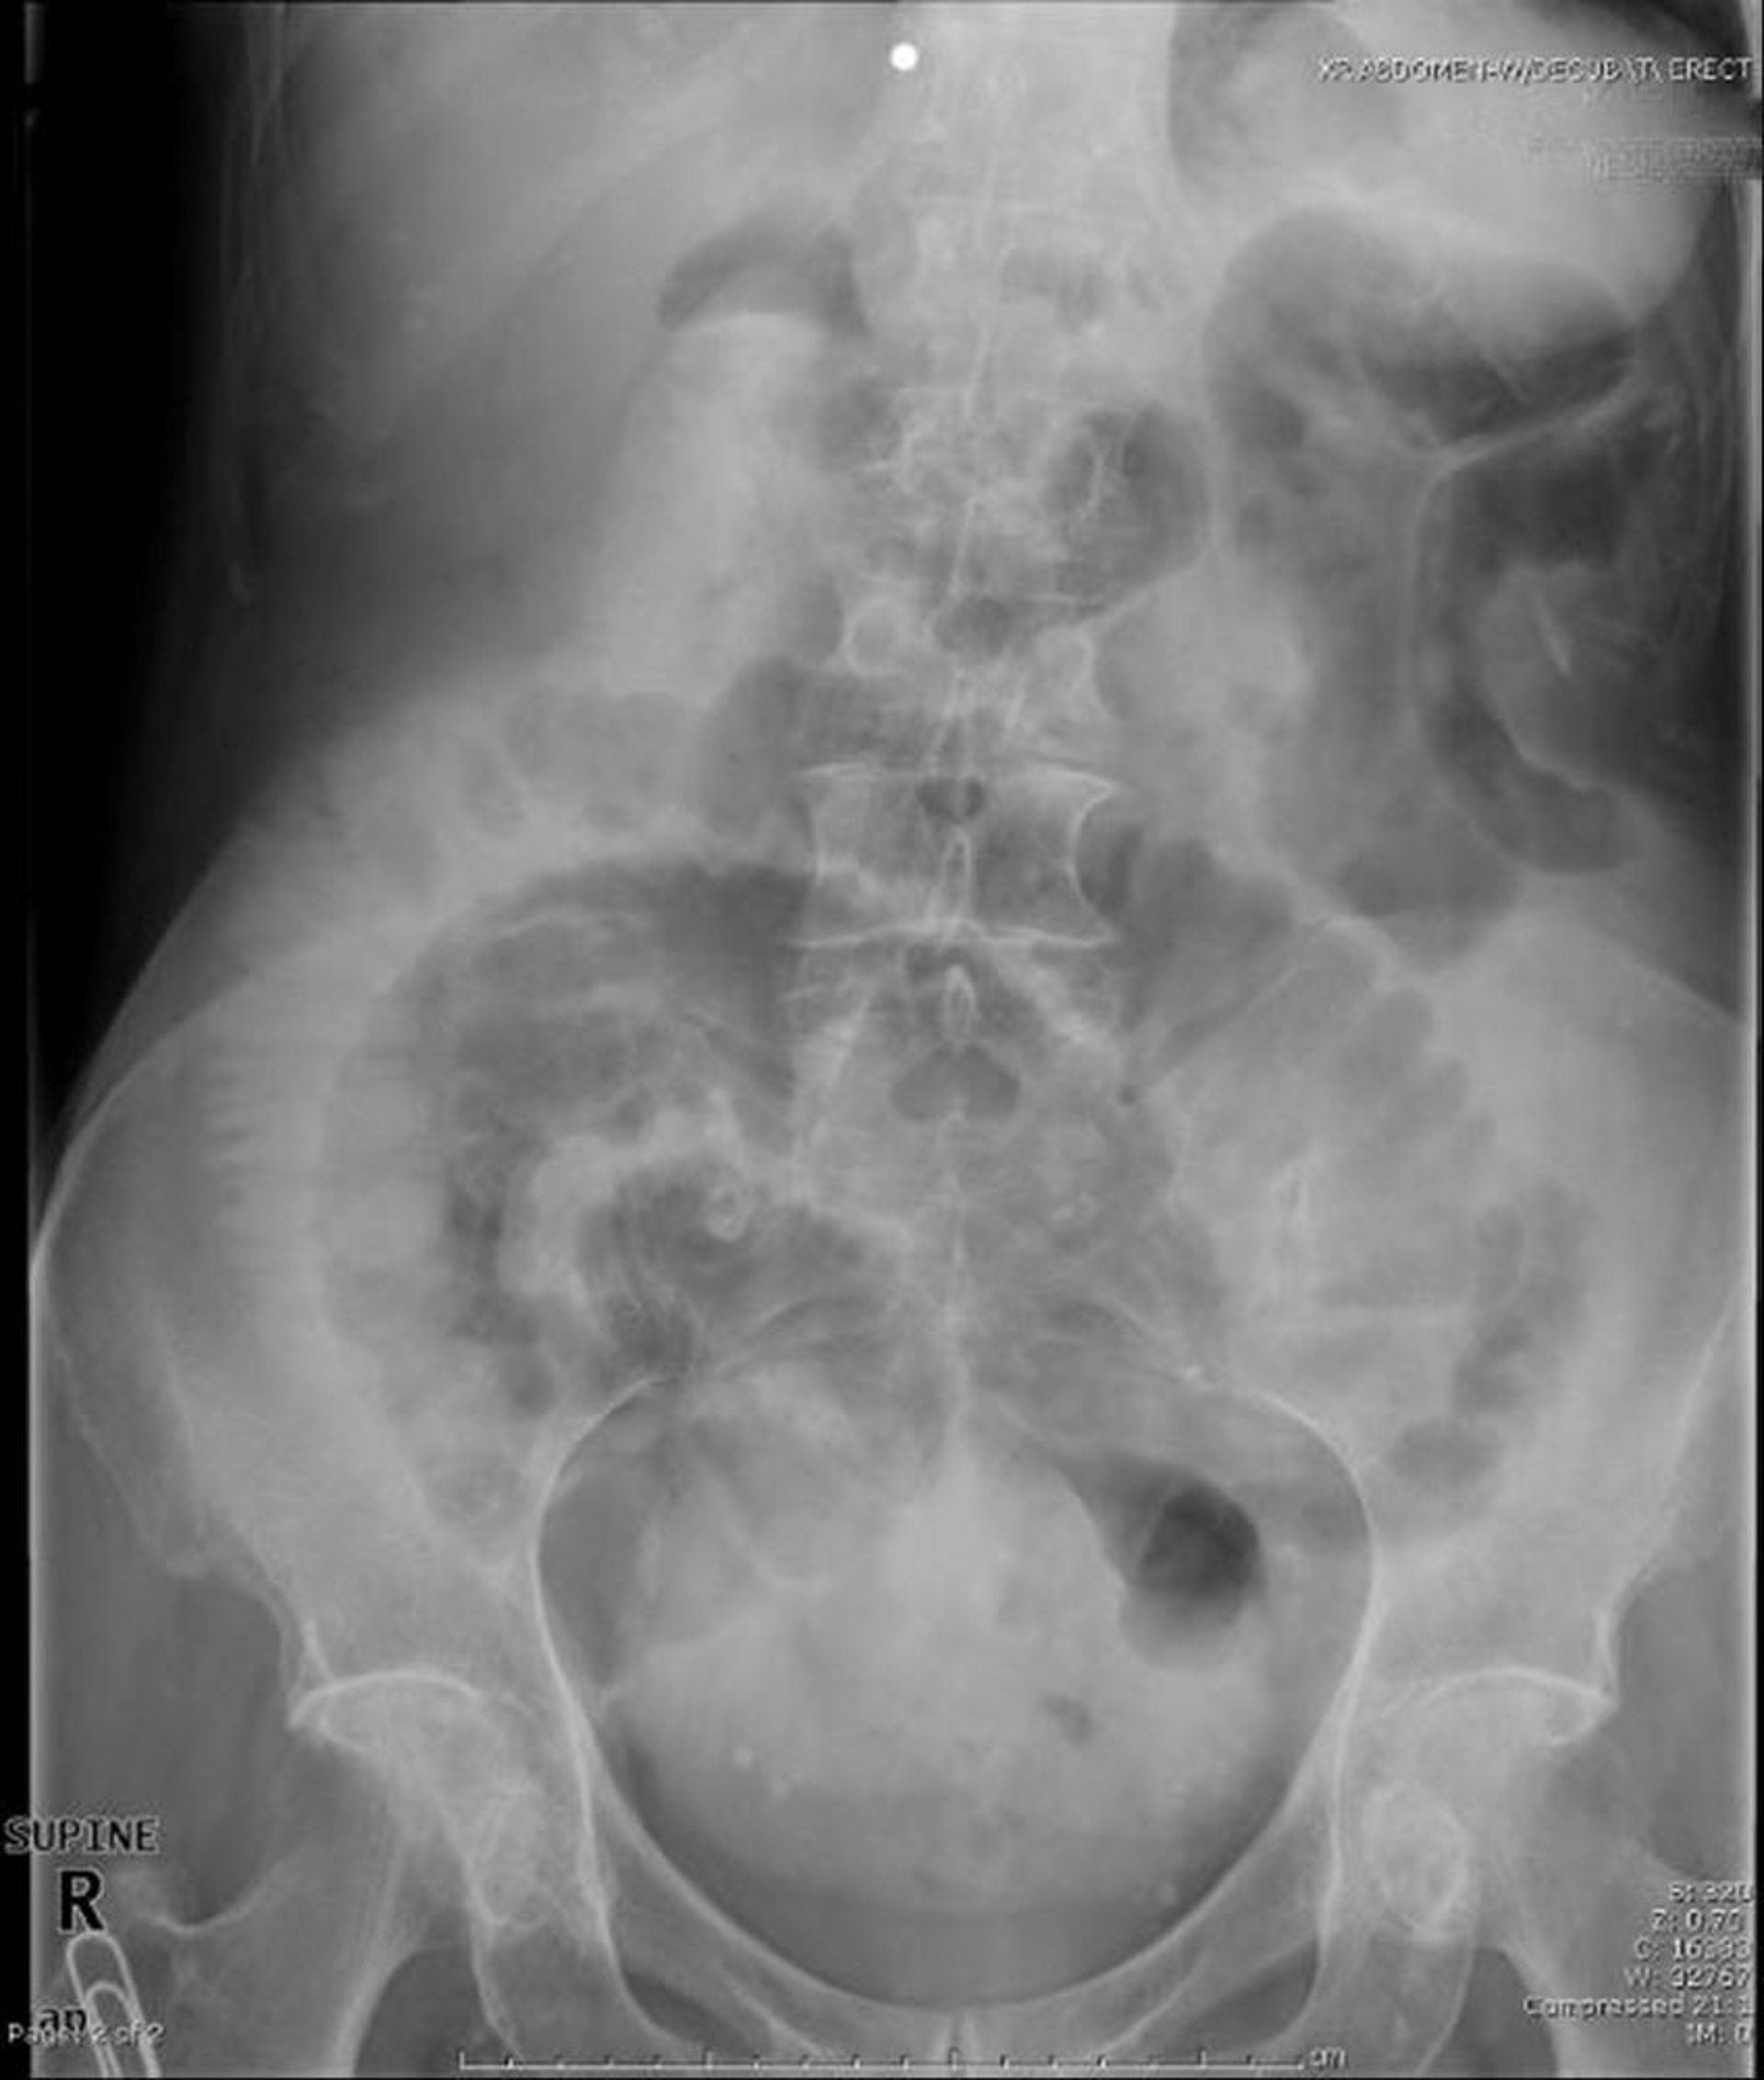

Occlusion de l'intestin grêle (radiographie couchée)

Cette radiographie en décubitus dorsal montre une obstruction de l'intestin grêle. Notez les anses dilatées de l'intestin grêle.

Image provided by Parswa Ansari, MD.